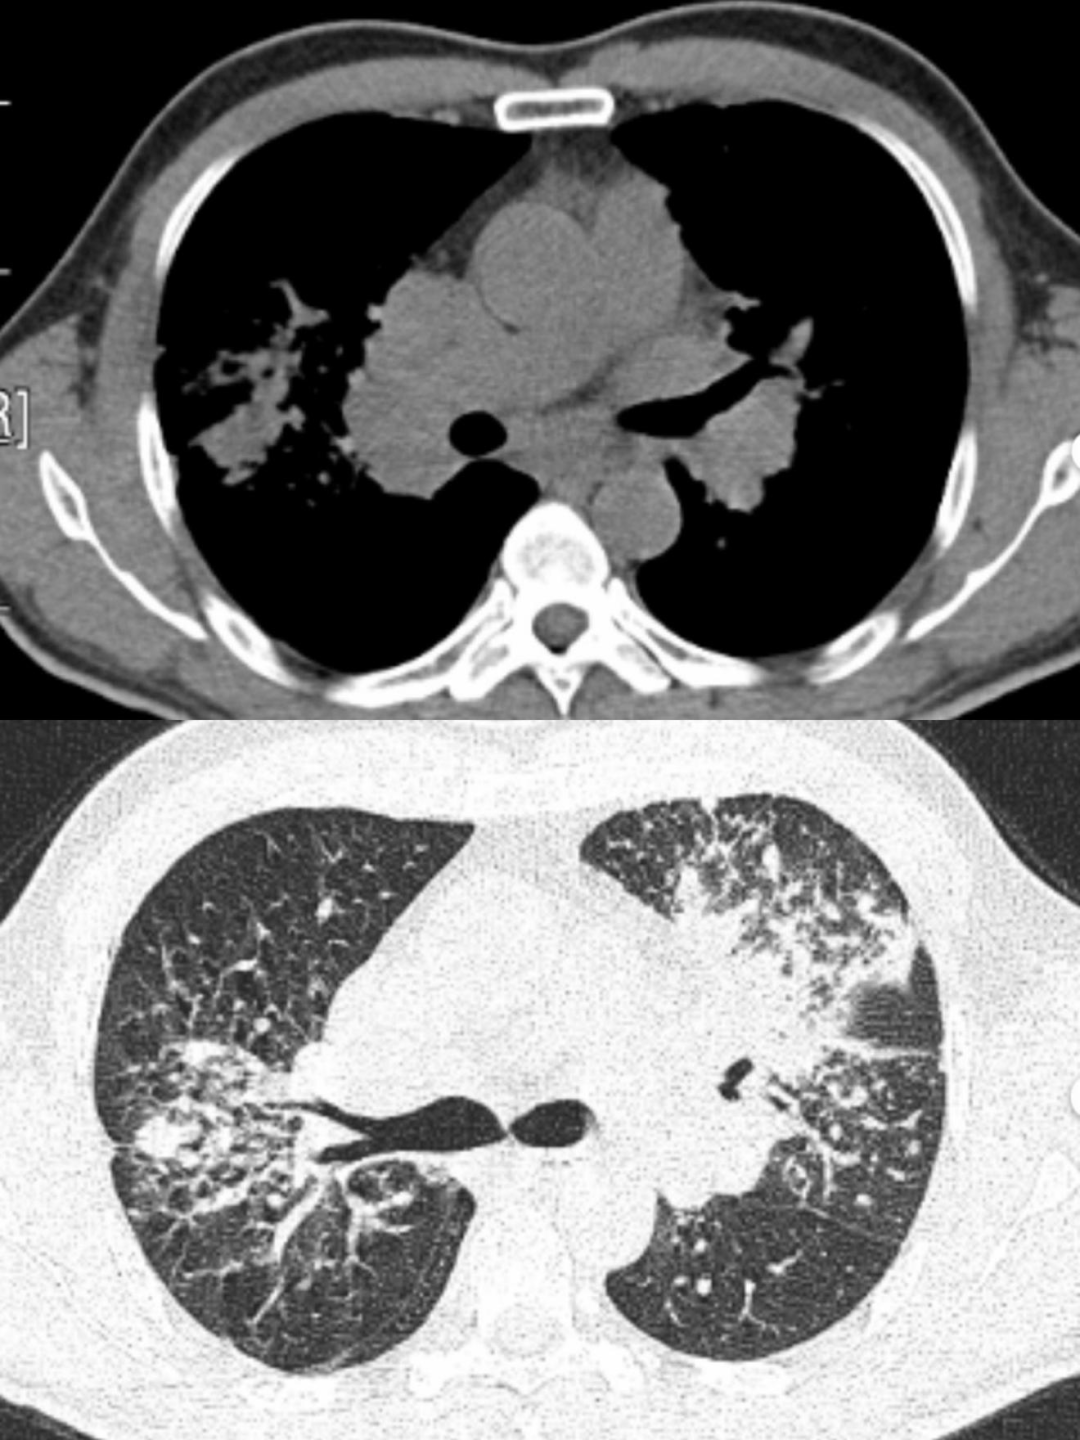

肺结节病

肺结节病诊断标准:

结节病属于排除性诊断,尚无客观诊断标准;可以基于如下三个主要条件:

1、具有相应的临床表现或(和)影像学特征。

2、至少一处受累部位的组织活检病理提示为非坏死性肉芽肿性炎。

3、除外其他原因所致的肉芽肿性疾病。